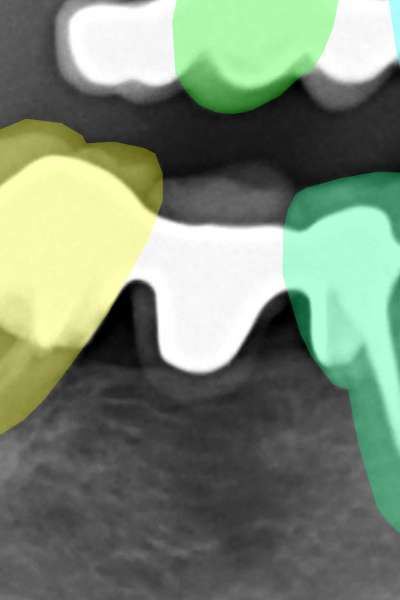

Figure 3 displays corresponding label samples of the aforementioned criteria. We followed the same criteria to label 400 additional images (40 per radiograph category). These images compounded our test set for assessing the neural networks trained at each HITL iteration.

Refer to caption

(a) Implants.

(b) Protheses.

(c) Molar roots.

(d) Restorations.

(e) Appliances.

Figure 3: Label samples of the employed criteria for annotating implants, prostheses, molar roots, restorations, and dental appliances. In general, the labels should be more refined on sharp and well-focused images, while in blurry images, the annotators should rely more on the tooth anatomical structures.